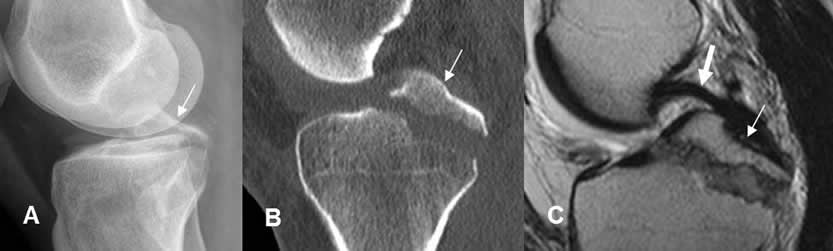

Fig 57 A. Fractura stress.

A: Rx AP, B: Rx oblicua y C: TAC reconstrucción lateral. Imagen en sentido transverso, sobre el tercio medio de la tibia, que corresponde a fractura de stress.